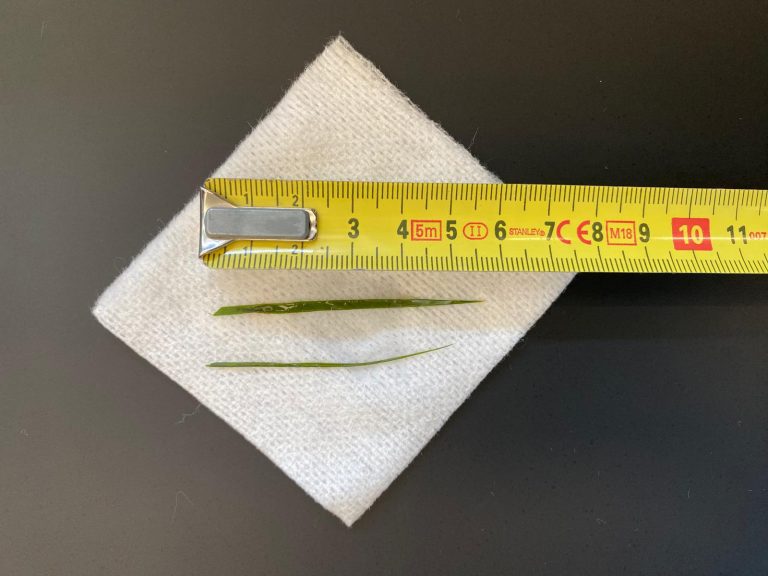

Om zeker te weten dat we alles hadden is het weefsel geopend, voordat we de wond gingen sluiten. In eerste instantie leek het alsof er geen grasaar in het weefsel zat. Maar dit liet maar weer zien hoeveel ons echoapparaat kan vergroten, want op de echobeelden is de diameter van de grasaar 1,5 millimeter en 12,4 millimeter lang. Na een paar sneden vonden we het steekkanaal en de daadwerkelijke grasaar.